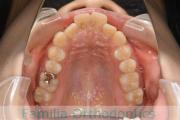

No.23V-385

- 主な症状:

- 叢生

- 年齢:

- 17歳

- 性別:

- 女性

- 抜歯部位

- 上:

- 44

- 下:

- 8448

- 主な使用装置:

- FEA 022

- 治療にかかった費用:

- 90万円

前歯のゆがみ、ズレがあるのを治したいということで来院されました。上下左右から小臼歯を抜歯して、マルチブラケット法にて治療をしました。1年8か月、20回程度の通院をしていただきました。叢生(でこぼこ、凹凸、ガタガタ)が強いため、保定をしっかりしないと後戻りのリスクがやや高いケースといえます。

- ≫治療前

上顎

下顎